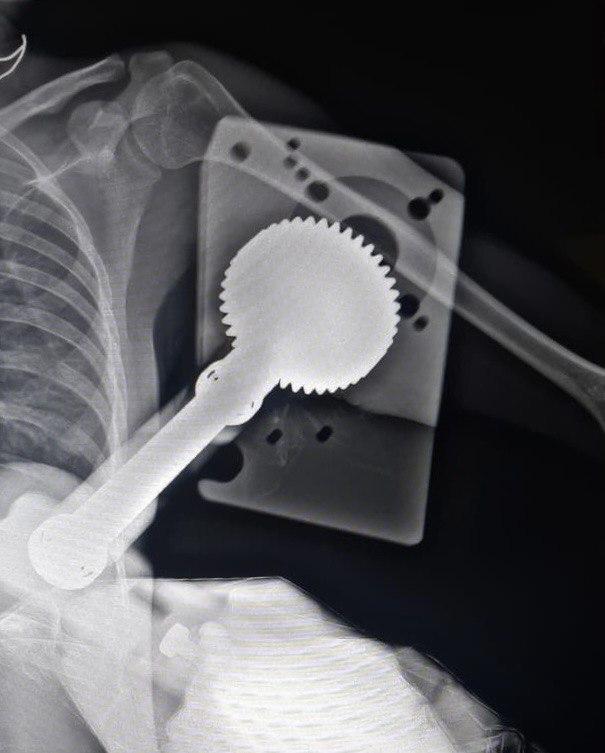

25-летняя пострадавшая поступила в медучреждение с обширной раной в области бицепса. Выяснилось, что она работала с зернодробильной машиной. В какой-то момент ее одежду, а затем и руку затянуло в работающий аппарат. Механизм прошел почти до плечевой кости, повредив мягкие ткани и мышцы. Медики приняли экстренное решение об операции.

Как сообщил заведующий травматологическим отделением Константин Смирнов, сначала врачи обработали хирургическим путем руку пациентки, после чего выделили зажатые и поврежденные сосудисто-нервные пучки. После этого специалисты достали из тканей застрявший механизм, сшили мышцы и устранили дефекты кожи с помощью пластики. Сообщается, что операция длилась около часа и закончилась успешно. В настоящий момент девушка чувствует себя хорошо, в скором времени ее выпишут из больницы.